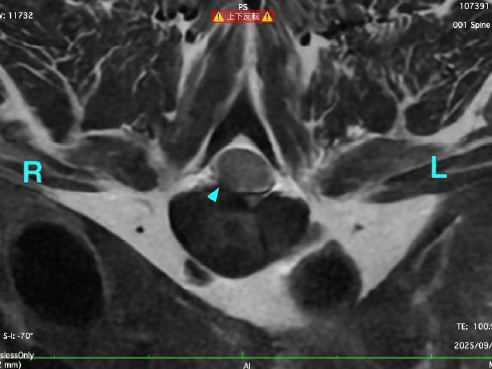

ある日、ワンちゃんが突然立てなくなった(起立困難)とのことで、当院に来院されました。 神経学的な検査を行ったところ、四肢すべてに麻痺が生じている疑いがあり、脊髄の障害が強く疑われました。 詳しく調べるために、麻酔下でMRI検査を実施した結果、第5?6頸椎に重度の椎間板ヘルニアが確認され、これが症状の原因(責任病変)と診断されました。 症状の発症から10日目に、神経の圧迫を取り除く手術(ベントラルスロット術)を実施しました。 手術の翌日には、自分で立ち上がることができるようになり、ふらつきながらも歩行が可能となったため、無事に退院となりました。

MRI検査による責任病変の評価